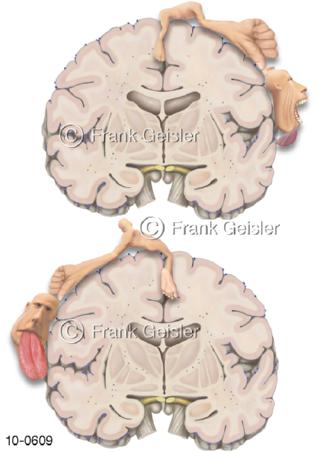

Bildergalerie Nervensystem

Bilder zum Nervensystem,dem Gehirn, Teil des zentralen Nervensystem, Zentralnervensystem ZNSmit Rückenmark, Abbildungen zum Nervengeflecht (Nervenplexus), die Verflechtungen von Nervenfasern, aus der Wirbelsäule hervortretende Nervenäst sowie Nervenzellen der Nerven